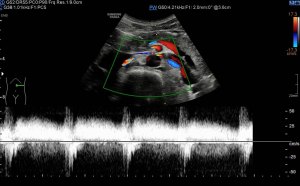

Los vientres anteriores de los músculos Digástricos, que son el objeto del desarrollo de este Post, son dos estructuras musculares redondeadas en el corte transversal, imagen 1, y alargados si los estudiamos en el eje largo, imagen 3, mira:

Ecográficamente los músculos digástricos en eje corto tienen semiología hipoecogénica, en aspecto de noche estrellada, como la de hoy, y en el eje largo en forma de penacho o en forma de plumas con las fibras alargadas y paralelas a la superficie.

Acostúmbrate a mirar esta anatomía en los estudios de cuello sobre todo en pacientes infantiles, por posible localización de adenopatías. En la edad adulta pueden objetivarse cambios de grosor, infrecuentemente, en esta musculatura por diferentes motivos.